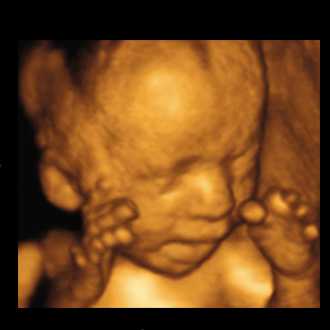

3D/4D SONOGRAPHY

3D/4D SONOGRAPHY (Live)

Built on a digital platform, the Voluson 730 utilizes advanced signal processing technology to ensure optimal image quality for high-resolution 2D, volumetric 3D and real-time 4D imaging. Image quality is further enhanced with Harmonic imaging, spectral, color and Doppler imaging,as well as our latest advance – Compound Resolution Imaging.

• High-resolution 2D, volumetric 3D and real-time 4D imaging